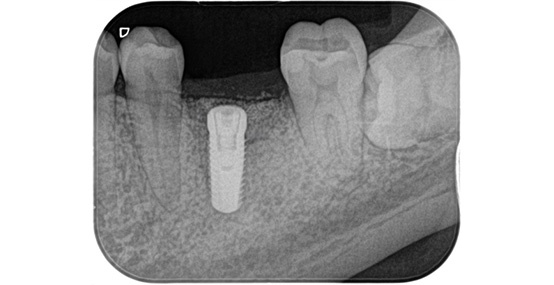

この症例では、抜歯する歯の周囲で骨が少し痩せている状態でした。

そのため、インプラントをしっかり支えるために、骨造成(骨を補う治療)を同時に行い、インプラントを埋入しました。

一次手術後のレントゲン写真です。

吸収していた骨の部分は人工の骨を足すことで無事に回復することができています。